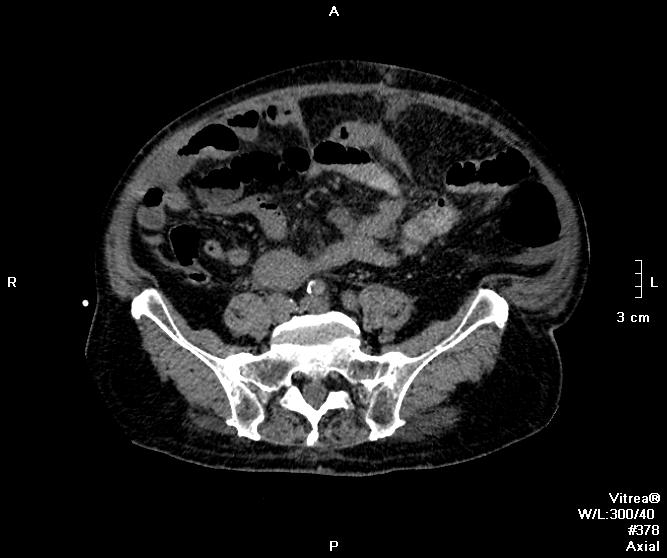

Пациент поступил ко мне через 6 дней после ушивания перфоративной язвы ДПК. УЗИ-сты увидели инфильтративно-жидкостные изменения в зоне оперативного вмешательства, пузырьки газа. Но смутило найденное образование в пространстве между правой долей печени и паранефрием. цель исследования - дифференцировать найденное между инфильтрацией и жидкостным скоплением.

Пациента готовили в течение 2 часов, перорально разведенный урографинчик дробно, и пол станканчика перед исследованием (это важно). Болюс в артериальную и венозную фазы.

мы имеем - задренированное околопеченочное пространство, жидкость в подпеченочном, левом поддиафрагмальном пространстве и по контурам селезенки (серозная), к передне-наружному контуру левой доли печени прилежит ограниченное жидкостное скопление

-ничего криминального между висцеральной поверхностью печени и правой почкой (паранефрий как им угодно) не вижу

-!!! в нативе желудок и петли кишечника не контрастированы - следы контраста в отдельных петлях тонкого к-ка (перед исследованиям он пил, по зонду ничего никуда - ни ни!!!), петли толстого и тонкого кишечника содержат умеренно повышенное количество воздуха и жидкого содержимого, с горизонтальными уровнями

- просвет верхне-горизонтальной ветви дпк в области оперативного вмешательства и зоны сегментарной пластики убудительно не прослеживаеся, представлен зоной инфильтрации, утолщенными стенками кишки, по наружному контуру воспаленных тканей лентовидно расположенные пузырьки воздуха - более вероятно воздух на фоне складок; затеков КВ нет

- воспалительные изменения в проекции лапаротомного доступа, в пжк передней брюшной стенки, в абдоминальной жировой клетчатке и межпетельно

- диверткулище мочевого пузыря

- инфильтрат в левой седалищно-прямокишечной ямке

- меня смущает не типичный вид артериальной фазы, и уж тем более венозной

Усиление коркового вещества слабое, задержка начала нефрографической фазы. диаметр почечным артерий около 5 мм, почечных вен -- 10мм. на 60 секунде отсутствует должное конрастирование вен, без признаков патологического сброса

и куда контраст делся из кишечника? (предположим - не развели в кувшинчике, но выпить-то перед исследованием мы ему дали)

ну не глюк ведь??? ни одна вена не усиливается! почему так???

Случай 1. Атеросклероз сосудов, запаздывание фаз секунд на 20-25. Получили раннюю артериальную фазу (посмотрите контрастирование камер сердца). И вместо портальной - нечто между поздней артериальной и портальной. Стоило, как мне кажется, сделать 85-90 сек, тогда бы попали в порталку.

По поводу жидкостей в брюшной полости (инфильтраты? где? Виталий показывает скопление жидкости у левой венечной связки) - нормальное послеоперационное их распределение, результат самой операции - т.е. лизированная кровь, ничего криминального, в соответствии с анатомией связок (в том числе и левой венечной, селезеночно-ободочной, желудочно-диафрагмальной)), обычная п/о реакция клетчатки. Абсцессов нет.

Инфильтрата в малом тазу (седалищно-прямокишечная ямка слева) тоже не увидела... немного жидкости стекло в таз после операции.